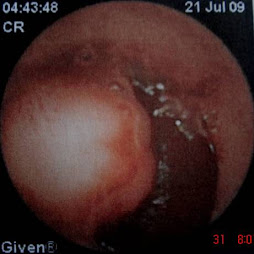

Enteroscopia doble balón: elevación submucosa ulcerada en yeyuno

Enteroscopia doble balón: lesión submucosa yeyunal

Enteroscopia doble balón: elevación submucosa ulcerada

Elevación submucosa ulcerada en yeyuno